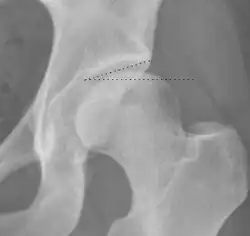

| Alpha angle | ![]() |

Degree of bulging of the femoral head-neck junction: In normal conditions there is a symmetric concave contour at the junction of the femoral head and neck. Loss of this concavity or bone bulging may lead to cam type impingement. The degree of this deformity can be measured by the alpha angle. Although it can be measured in the cross-lateral view, the 45° Dunn view is considered more sensitive and the frog leg view more specific in determining pathologic values. |

|